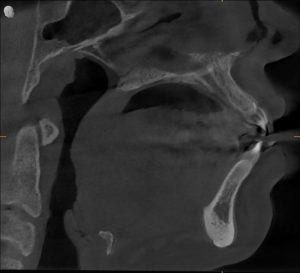

CBCT & Cephalometry

- Mild airway constriction

- Mild maxillary constriction

- Normal jaw structure

- No skeletal airway deficiency